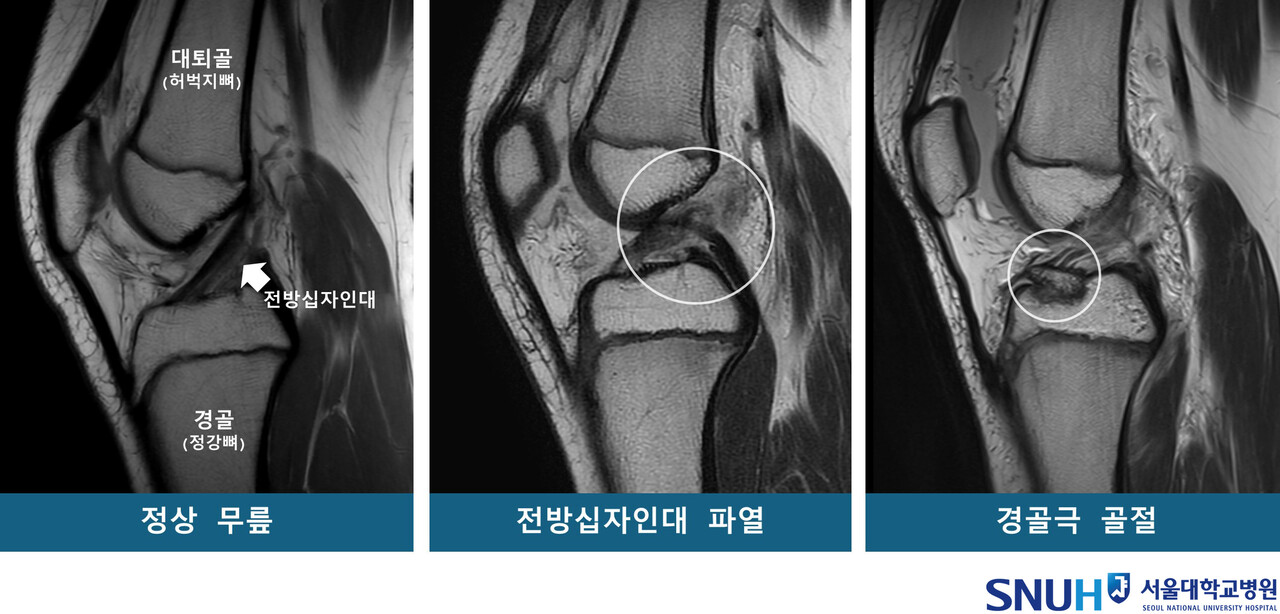

교수팀에 따르면 소아청소년은 뼈와 근육 발달이 미성숙해 스포츠 손상에 취하며, 특히 ‘전방십자인대 파열’과 ‘경골극 골절’은 소아청소년에게 발생하기 쉬운 대표적인 무릎 손상이다.

구체적으로 소아청소년을 53명씩 △전방십자인대 파열군 △경골극 골절군 △대조군(정상 무릎)으로 구분하고 연령·성별을 매칭하고, MRI를 재구성한 3차원 영상을 바탕으로 14개의 해부학적 지표를 분석했다.

그 결과, 두 무릎 손상군은 대조군보다 ‘경골 바깥쪽 관절면 경사’가 유의미하게 높았다. 통계 분석에 따르면 경사가 높을수록 전방십자인대 파열 및 경골극 골절 발생 위험이 각각 1.42배·1.33배 증가했으며, 이 값이 소아청소년의 주요 무릎 손상에 대한 위험인자인 것으로 나타났다.

반면, ‘대퇴과간 절흔 폭(무릎뼈 사이 공간)’은 전방십자인대 파열군에서만 유의미한 연관성이 있었다. 특히 이 폭이 넓을수록 파열 위험이 감소하는 보호 효과가 확인됐다.

교수팀은 “경골 바깥쪽 관절면의 경사가 가파를수록 무릎에 무게가 실릴 때 대퇴골이 바깥쪽으로 회전하며, 그 결과 전방십자인대가 과부하돼 파열이나 경골극 골절로 이어질 수 있다”며 “또한 대퇴과간 절흔 폭이 넓을 경우, 전방십자인대가 대퇴골과 덜 충돌하기 때문에 파열 위험이 낮아지는 경향이 있다”고 설명했다.